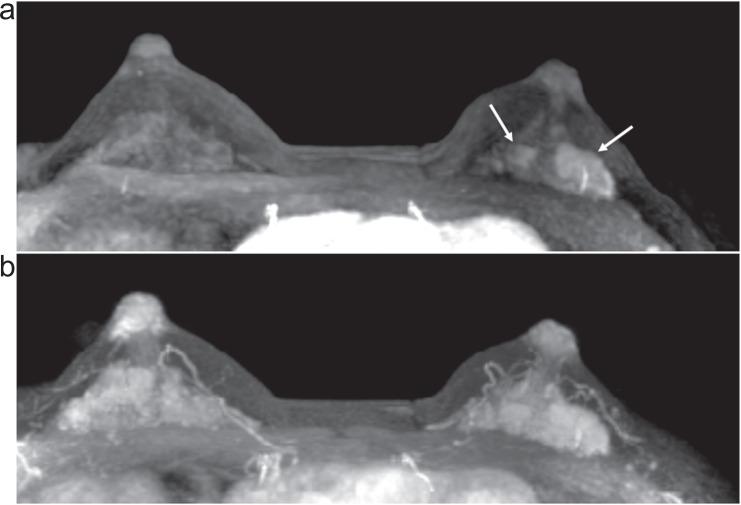

Ultrafast dynamic contrast-enhanced (UF-DCE) MRI is a new approach to capture kinetic information in the very early post-contrast period with high temporal resolution while keeping reasonable spatial resolution. The detailed timing and shape of the upslope in the time-intensity curve are analyzed. New kinetic parameters obtained from UF-DCE MRI are useful in differentiating malignant from benign lesions and in evaluating prognostic markers of the breast cancers. Clinically, UF-DCE MRI contributes in identifying hypervascular lesions when the background parenchymal enhancement (BPE) is marked on conventional dynamic MRI. This review starts with the technical aspect of accelerated acquisition. Practical aspects of UF-DCE MRI include identification of target hypervascular lesions from marked BPE and diagnosis of malignant and benign lesions based on new kinetic parameters derived from UF-DCE MRI: maximum slope (MS), time to enhance (TTE), bolus arrival time (BAT), time interval between arterial and venous visualization (AVI), and empirical mathematical model (EMM). The parameters derived from UF-DCE MRI are compared in terms of their diagnostic performance and association with prognostic markers. Pitfalls of UF-DCE MRI in the clinical situation are also covered. Since UF-DCE MRI is an evolving technique, future prospects of UF-DCE MRI are discussed in detail by citing recent evidence. The topic covers prediction of treatment response, multiparametric approach using DWI-derived parameters, evaluation of tumor-related vessels, and application of artificial intelligence for UF-DCE MRI. Along with comprehensive literature review, illustrative clinical cases are used to understand the value of UF-DCE MRI.